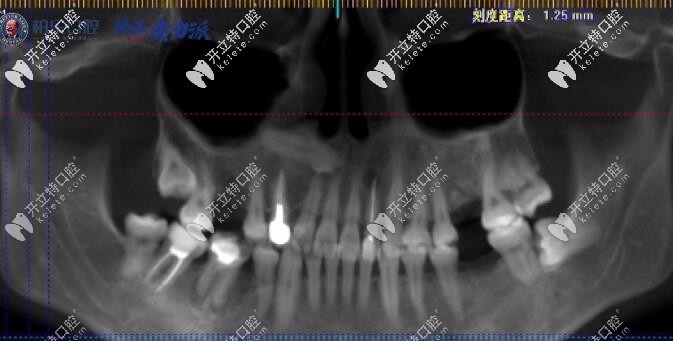

后牙缺了幾顆怎么修復(fù)?看30歲的顧客大牙缺三顆也能做牙齒矯正;這份南寧柏樂口腔醫(yī)院矯正案例,你看了也會驚訝:原來缺牙不是只能做種植牙也可以通過矯正關(guān)閉牙齒縫隙。